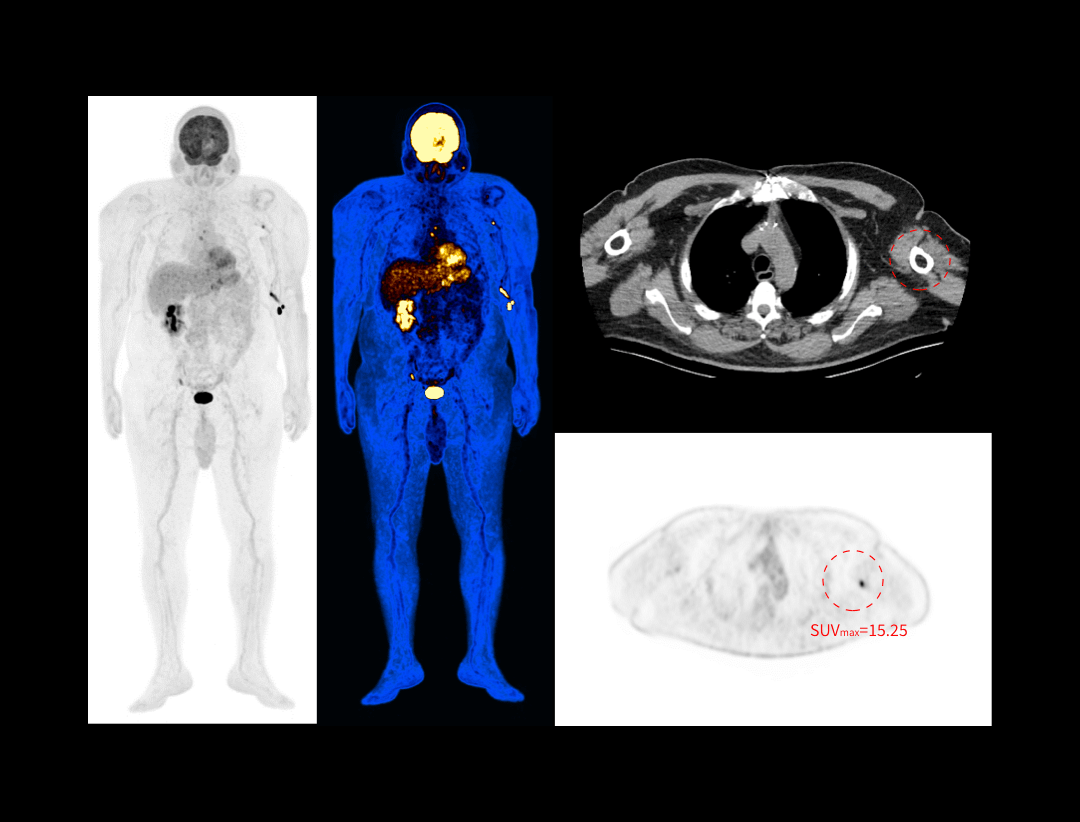

Galerie clinică

Scanare întregului corp în 8 minute

Imagistică PET/CT pentru pacienți cu indice BMI de 40,3

Scanare FDG la 0,05 mCi/kg

Detectarea leziunilor mici de 2,2 mm

Imagistică cerebrală de înaltă rezoluție

Limfom gastric evaluat prin FDG